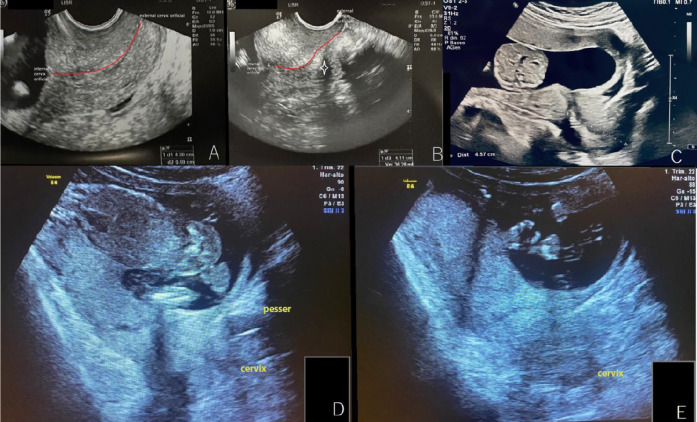

Manual reduction in conjunction with Arabin pessary to reduce first trimester urinary retention relapse.

人工减量联合阿拉宾可减少妊娠早期尿潴留复发。